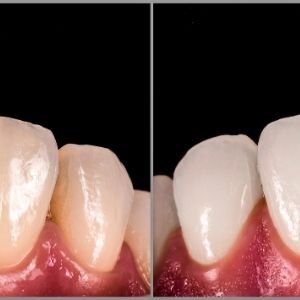

Blanqueamiento

Con el paso del tiempo, los dientes adquieren un color amarillento o marrón por diversos motivos: técnica inadecuada de cepillado o higiene bucal deficiente, consumo de ciertos productos (vino, te, café, cúrcuma, tabaco), por consumo de medicamentos, traumatismo dental etc., el cual se analiza en consulta de diagnóstico y se recomienda el blanqueamiento adecuado a cada caso.

Se lleva a cabo en la clínica dental la aplicación de un agente blanqueador en el cual es necesario realizar previamente una profilaxis dental y confirmar que la cavidad oral se encuentre sana, principalmente sin gingivitis, caries dental o restauraciones fracturadas para tener resultados satisfactorios. En algunas veces se puede recomendar una técnica inmediata y una técnica ambulatorio.